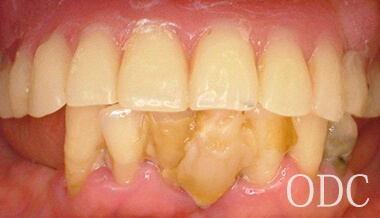

All-on-4 CASE.1

BEFORE AFTER

オールオンフォー症例1-1 オールオンフォー症例1-3 オールオンフォー症例1-2 オールオンフォー症例1-4